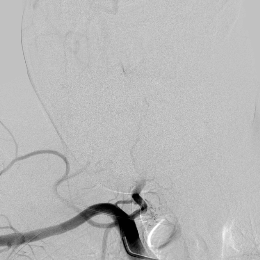

相逢就是缘,有求必全力以赴。立即进行全面评估,CTA和MRI发现颅内多发脑梗塞,脑干为重,双侧椎动脉颅内段基本看不到了,而进一步的DSA造影更为糟糕,左侧椎动脉的颅内颅外段直接全程完全闭塞,右侧颅外剩下一个小尾巴在血液中摇摇欲坠……,诺大的后循环仅仅靠纤细的后交通动脉从前循环借点血液过来,勉强续命,仅仅靠这点前循环的救急,可谓“杯水车薪”,不是“长久之计”,于是决定开通右侧闭塞的椎动脉(颅内+颅外,主要集中在V3+V4段)。

开通这么长节段的夹层所致的椎动脉,说说可以,做起来绝非易事,特别是颅内段,一旦跑到血管外出血,接近脑干,后果严重,谨慎开通的过程还算顺利,微导管带过就是磕磕绊绊不顺利,好吧,小球囊从上到下扩下来,不通,更换稍大球囊扩下来,还是不通,这夹层和狭窄不一样啊,支架导管带过仍然磕磕绊绊,不顺畅,铺开第一个支架,直接来了末端打开不良……,这么长的闭塞段,那得需要多少支架啊?万一放完了,钱花了,不通咋办?

微导管继续超过去,轻轻造影,开通的路径隐约返流闪现,立即改变策略,逆向铺路,开通成功。